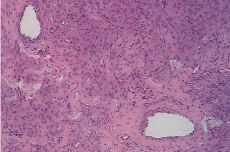

El nódulo resecado correspondía a un tumor de consistencia firme, redondeado, de 6 x 5 x 5 cm, circunscrito, con superficie de corte homogénea (Fig. 1). El estudio histológico demostró que estaba constituido por una proliferación de células alargadas, distribuidas en fascículos (Fig. 2), sin atipias ni mitosis. En algunos campos, eran llamativos vasos sanguíneos grandes (Fig. 3). En un punto, el tumor mostraba un patrón tubular, que recordaba a los tumores adenomatoides del tracto genital (Fig. 4).

Figura 3.La fotografía ilustra dos vasos prominentes en el seno del tejido muscular. Hematoxilina-Eosina, 100 x.